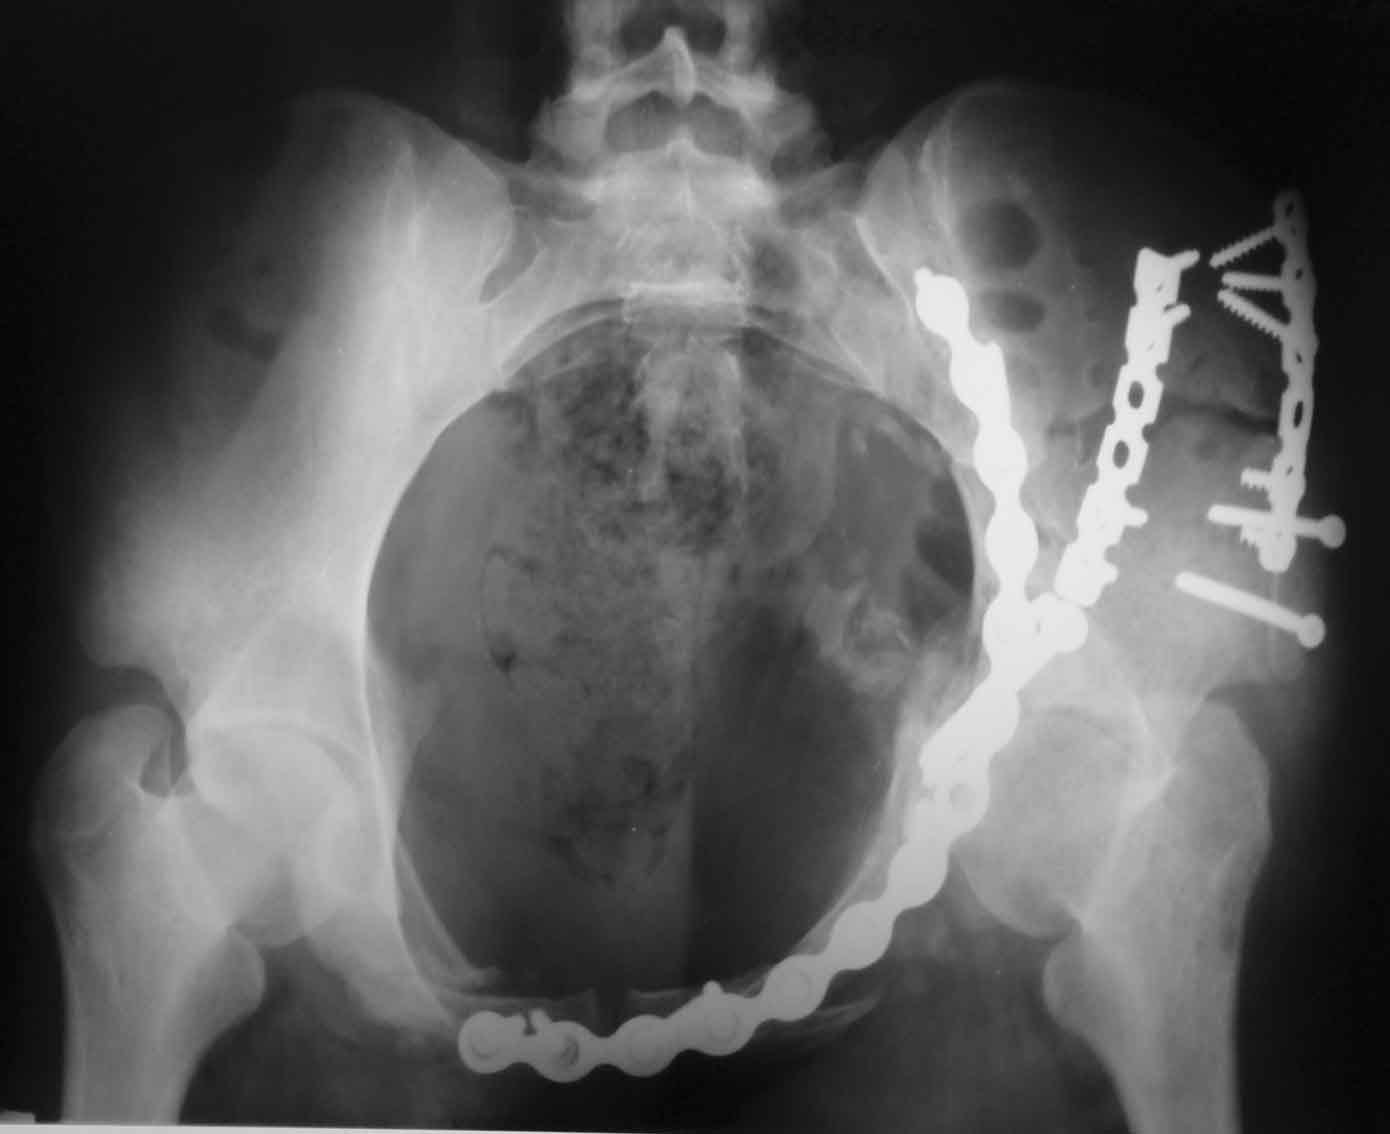

Рентгенограмма после операции. Изв. за качество. На днях переделаем.

Рентгенограммы после операции

Прямая проекция

inlet

подвздошная

запирательная